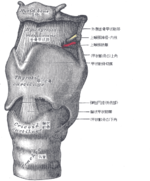

樋状根(といじょうこん)

下顎の7番に多く、日本人の2~3割に存在すると言われています。

歯の神経が存在しているとことが特殊な形態をしていて、非常に治療が難しい歯の一つです。

でも、綺麗に根充はできました。 (あとは、根管内の洗浄がしっかりできていて、無菌化できていれば完璧です)

(あとは、根管内の洗浄がしっかりできていて、無菌化できていれば完璧です)